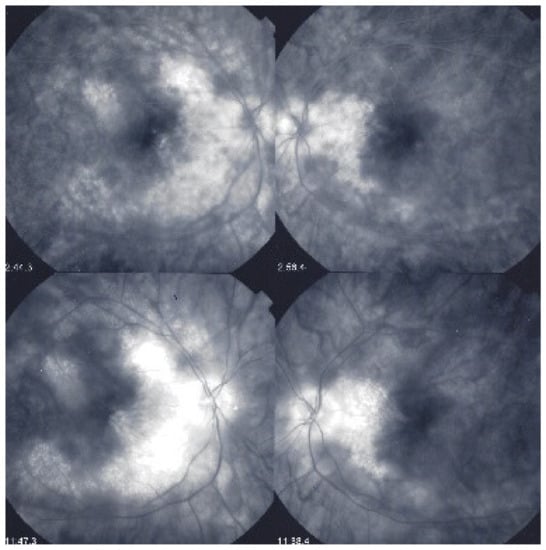

As for all PICCPs, multimodal imaging is best accounting for MFC features (Table 4). On ICGA, the first set of signs identifies old scarred chorioretinal lesions and consists of hypofluorescent areas persisting up to the late angiographic phase, distributed at random in the fundus, corresponding to late hyperfluorescence on FA, typical for chorioretinal atrophy from scars of previous inflammatory episodes seen on colour fundus photos. The second set of signs can be seen in addition to the previously described signs when choroiditis recurs or can be seen in the absence of scars when it is the first episode. The signs consist of hypofluorescent areas, either silent on fluorescein angiography or hyperfluorescent in the late phase and usually not visible on fundus examination, representing areas of new inflammatory involvement (Figure 14). As in many PICCPs, some cases may present peripapillary hypofluorescence, translating functionally into an enlarged blind spot [18,36,54,55] (Figure 15). The hypofluorescent areas can completely regress if inflammation suppressive treatment is started promptly. In a substantial proportion of cases, the extent of ICGA hypofluorescence reflecting choriocapillaris hypoperfusion or nonperfusion is far more widespread than visible lesions let suspect, showing widespread areas of late occult hypofluorescence with absolutely no signs visible on fundus examination or on fluorescein angiography (Figure 15).